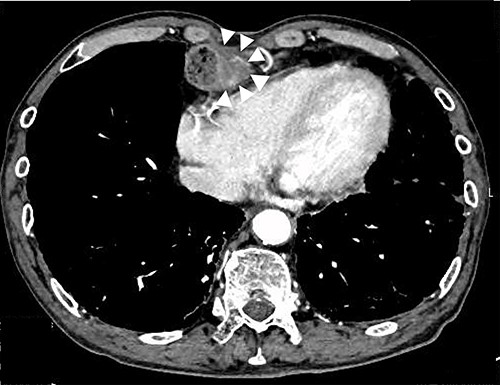

Upper gastrointestinal endoscopy at the seventh year of follow-up revealed a polypoid tumor of 3 cm in diameter at the pyloric region of the gastric tube with pyloric obstruction (Fig. 1). Endoscopic biopsy from the tumor revealed papillary adenocarcinoma (pap > tub1). Contrast-enhanced computed tomography (CT) demonstrated a solid mass with slight enhancement at the abdominal part of the gastric tube located below the lower border of the sternum (Fig. 2). Neither lymph node metastasis nor distant metastasis was detected, leading to a diagnosis of clinical stage IB (cT2N0M0) gastric cancer according to the seventh edition of the Union for International Cancer Control system.

Preoperative CT image; white arrows indicate a tumor with thickening of the gastric wall.